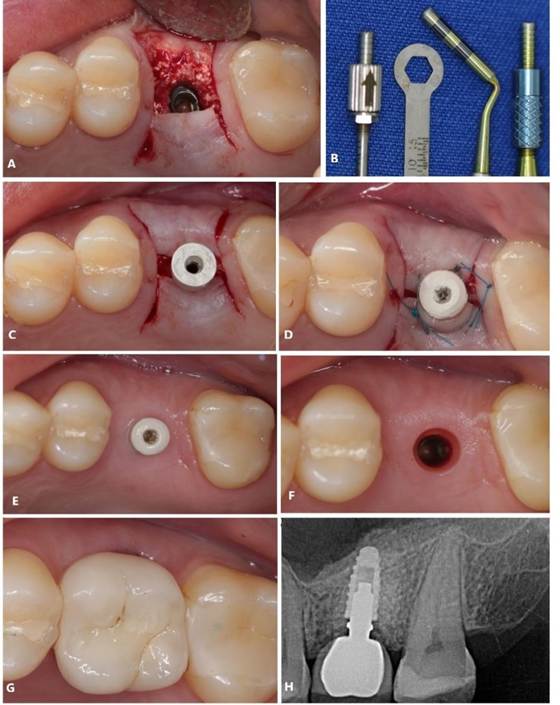

Foram solicitados exames complementares, incluindo radiografia panorâmica e tomografia computadorizada, para avaliação precisa da região anatômica, permitindo a quantificação da espessura e altura óssea (Figura 01. A-D). O plano de tratamento consistiu pela instalação de implantes ultrashort ARCSYS (FGM, Joinvile – SC, Brasil) 4,3 mm x 5,0 mm.

Inicialmente o bloqueio regional foi realizado utilizando anestésico local Alphacaíne 2% Lidocaína com Epinefrina 1:100.000 (DFL, Rio de Janeiro – RJ, Brasil). O procedimento cirúrgico seguiu-se pela incisão da região com lâmina 15, descolamento com instrumental Molt 9 (Quinelato, Rio Claro – SP, Brasil) e fresagem com broca Titamax 2.0 (Neodent, Curitiba – PR, Brasil), seguindo a sequência recomendada pelo fabricante. Após a instalação do implante curto, a sutura foi realizada com fio de nylon 4.0. O paciente foi instruído dos cuidados pós-operatórios, com prescrição medicamentosa de Amoxicilina 500mg de 8/8 horas por 7 dias, Nimesulida 100mg de 12/12 horas por 5 dias e Dipirona sódica 500mg de 4/4 horas por 3 dias. Ausência de complicações pós-operatórias foram evidenciadas (Figura 02. A,B)

Posteriormente, paciente foi reabilitado com prótese unitária sobre implantes (Figura 02. C,D) e o acompanhamento clínico e radiográfico (Figura 03. A, B) está sendo realizado até o presente momento, evidenciado resultado estável.

Figura 01. A – D) Exames de imagem complementares evidenciado aspecto inicial da região atrófica na maxila superior direita (área do elemento dental 16).

Figura 02. A, B) Etapa operatória da instalação do implante dental curto. C, D) Tratamento finalizado. Aspecto final com a reabilitação protética-implante.

Figura 03. A, B) Radiografias periapicais final.